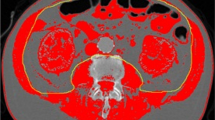

The results of multiple logistic regression test are presented in Table 2. Coronary artery disease, respiratory rate, lactate and SOFA score were not predictive of 28-day mortality. The difference of TAMAI using the optimal cut-off value (6.4 cm2/m2) was the only independent predictor for 28-day mortality (OR, 4.42; 95% CI, 1.41–13.81, p = 0.011), and with high goodness-of-fit of the model (p > 0.05). There was no significant multicollinearity. These results suggested that progressive muscle loss can be used as a prognostic factor to predict 28-day mortality, as illustrated in the representative cases (Fig. 4).

Representative cases with and without progressive sarcopenia. (A) A 70 year old female with progressive sarcopenia. During treatment of biliary liver cirrhosis (asterisks) with steroid, sarcopenia was aggravated (TAMAI; 35.91 on Feb 2013 and 19.38 on July 2013). On July 2013, pneumonia occurred due to septic embolism (arrows). She was admitted to intensive care unit and treated with antibiotics. However, she was expired after 2 days. (B) A 54 year old female without progressive sarcopenia. During chemotherapy for stomach cancer with peritoneal carcinomatosis (arrows), the muscle mass was not changed (TAMAI; 38.83 on May 2013 and 35.56 on Aug 2013). On Aug 2013, sepsis shock occurred due to urosepsis with hydronephrosis (arrowheads). She was admitted to intensive care unit and treated with double-J stent insertion, percutaneous nephrostomy, and antibiotics. After 10 days, she was recovered.

Imaging and assessment of muscle mass

Body mass index (BMI) was defined as the weight in kilograms divided by the square of the height in meters (kg/m2)15,40 and was categorized as underweight (BMI <20.0 kg/m2), normal weight (BMI 20.0 to 24.9 kg/m2), overweight (BMI 25.0 to 29.9 kg/m2), or obese (BMI ≥30.0 kg/m2)15. Body composition was evaluated using CT images acquired during underlying disease treatment and follow-up. An experienced radiologist (K.W.K), who was blind to clinical information performed the image analysis using AsanJ-MorphometryTM software. This is dedicated software for measuring abdominal muscle and fat area based on ImageJ (NIH, Bethesda, MD, USA)41.

As described in the previous work, the inferior endplate level of the L3 vertebra was chosen as a landmark because it correlates with whole-body skeletal muscle mass and adipose-tissue mass42. Total abdominal muscle area (TAMA), including all muscles on the selected axial images, i.e., psoas, paraspinal, transversus abdominis, rectus abdominis, quadratus lumborum, and internal and external obliques, were demarcated using predetermined thresholds (−29 to +190 Hounsfield units). The visceral fat area (VFA) and the subcutaneous fat area (SFA) were also demarcated using fat tissue thresholds (−190 to −30 Hounsfield units). The TAMA was normalized for the square of the height (expressed in units of cm2/m2) and was referred to as the TAMA index (TAMAI). According to Martin’s study, in women, low TAMAI was defined as <41 cm2/m2 regardless of BMI15. For men, low TAMAI was defined as <43 cm2/m2 when BMI was <25 kg/m2, and <53 cm2/m2 when BMI was 25 kg/m2 or more15. TAMAI difference was calculated by subtracting the TAMAI value of the second CT (CT image at septic shock diagnosis) from that of the first CT (CT image of 90–180 days before septic shock diagnosis).